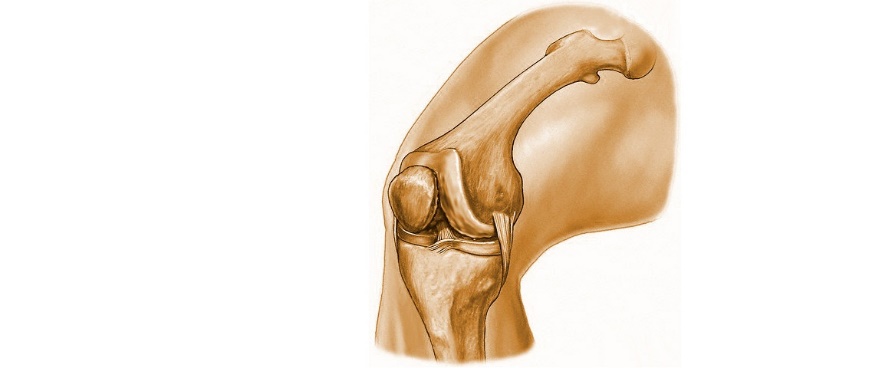

Рисунки Суставов: Анатомические Иллюстрации